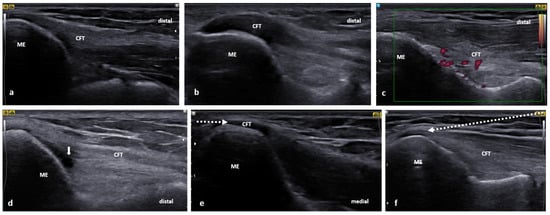

3.2. Golfer’s Elbow

3.2.2. US scanning and Guided Injection